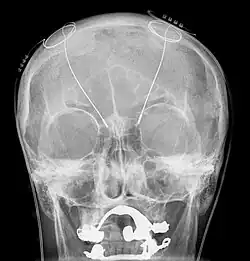

Электроды ГСМ (глубокая стимуляция мозга, англ. Deep brain stimulation, DBS) на рентгеноскопическом снимке черепа человека.

Развитие компьютерных технологий открыло новую эру в лечении пациентов, страдающих болезнью Паркинсона. Всё чаще применяется новый метод глубокой стимуляции мозга (ГСМ). Метод ГСМ заключается в использовании импульсов электрического стимулятора, встроенного поверхностно в организм пациента. Через введённый в мозг специальный электрод импульсы подаются в базальные ганглии, в частности, в субталамические ядра, и выполняют высокочастотную стимуляцию групп нейронов, что приводит к заметному улучшению перенесения болезни. Вследствие существенного ослабления симптомов болезни, пациенты могут вернуться к нормальной повседневной деятельности и значительно уменьшить объём употребления лекарств. Кроме болезни Паркинсона, показаниями к операции являются врожденные дистония и эссенциальный тремор[31]. Также продолжаются клинические испытания для применения ГСМ в лечении депрессии.